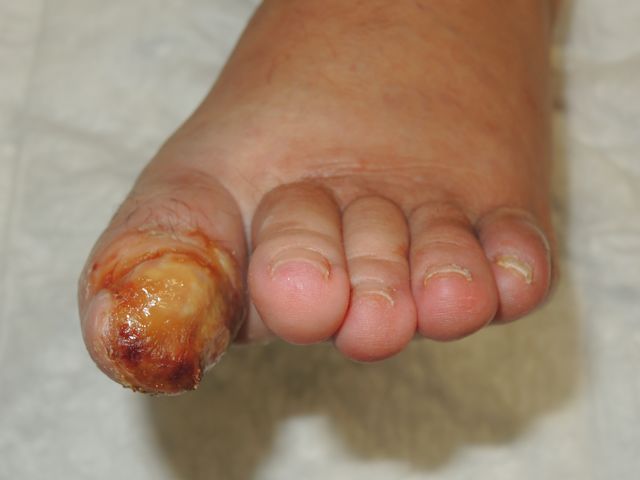

Ulceraciones en pie diabético.